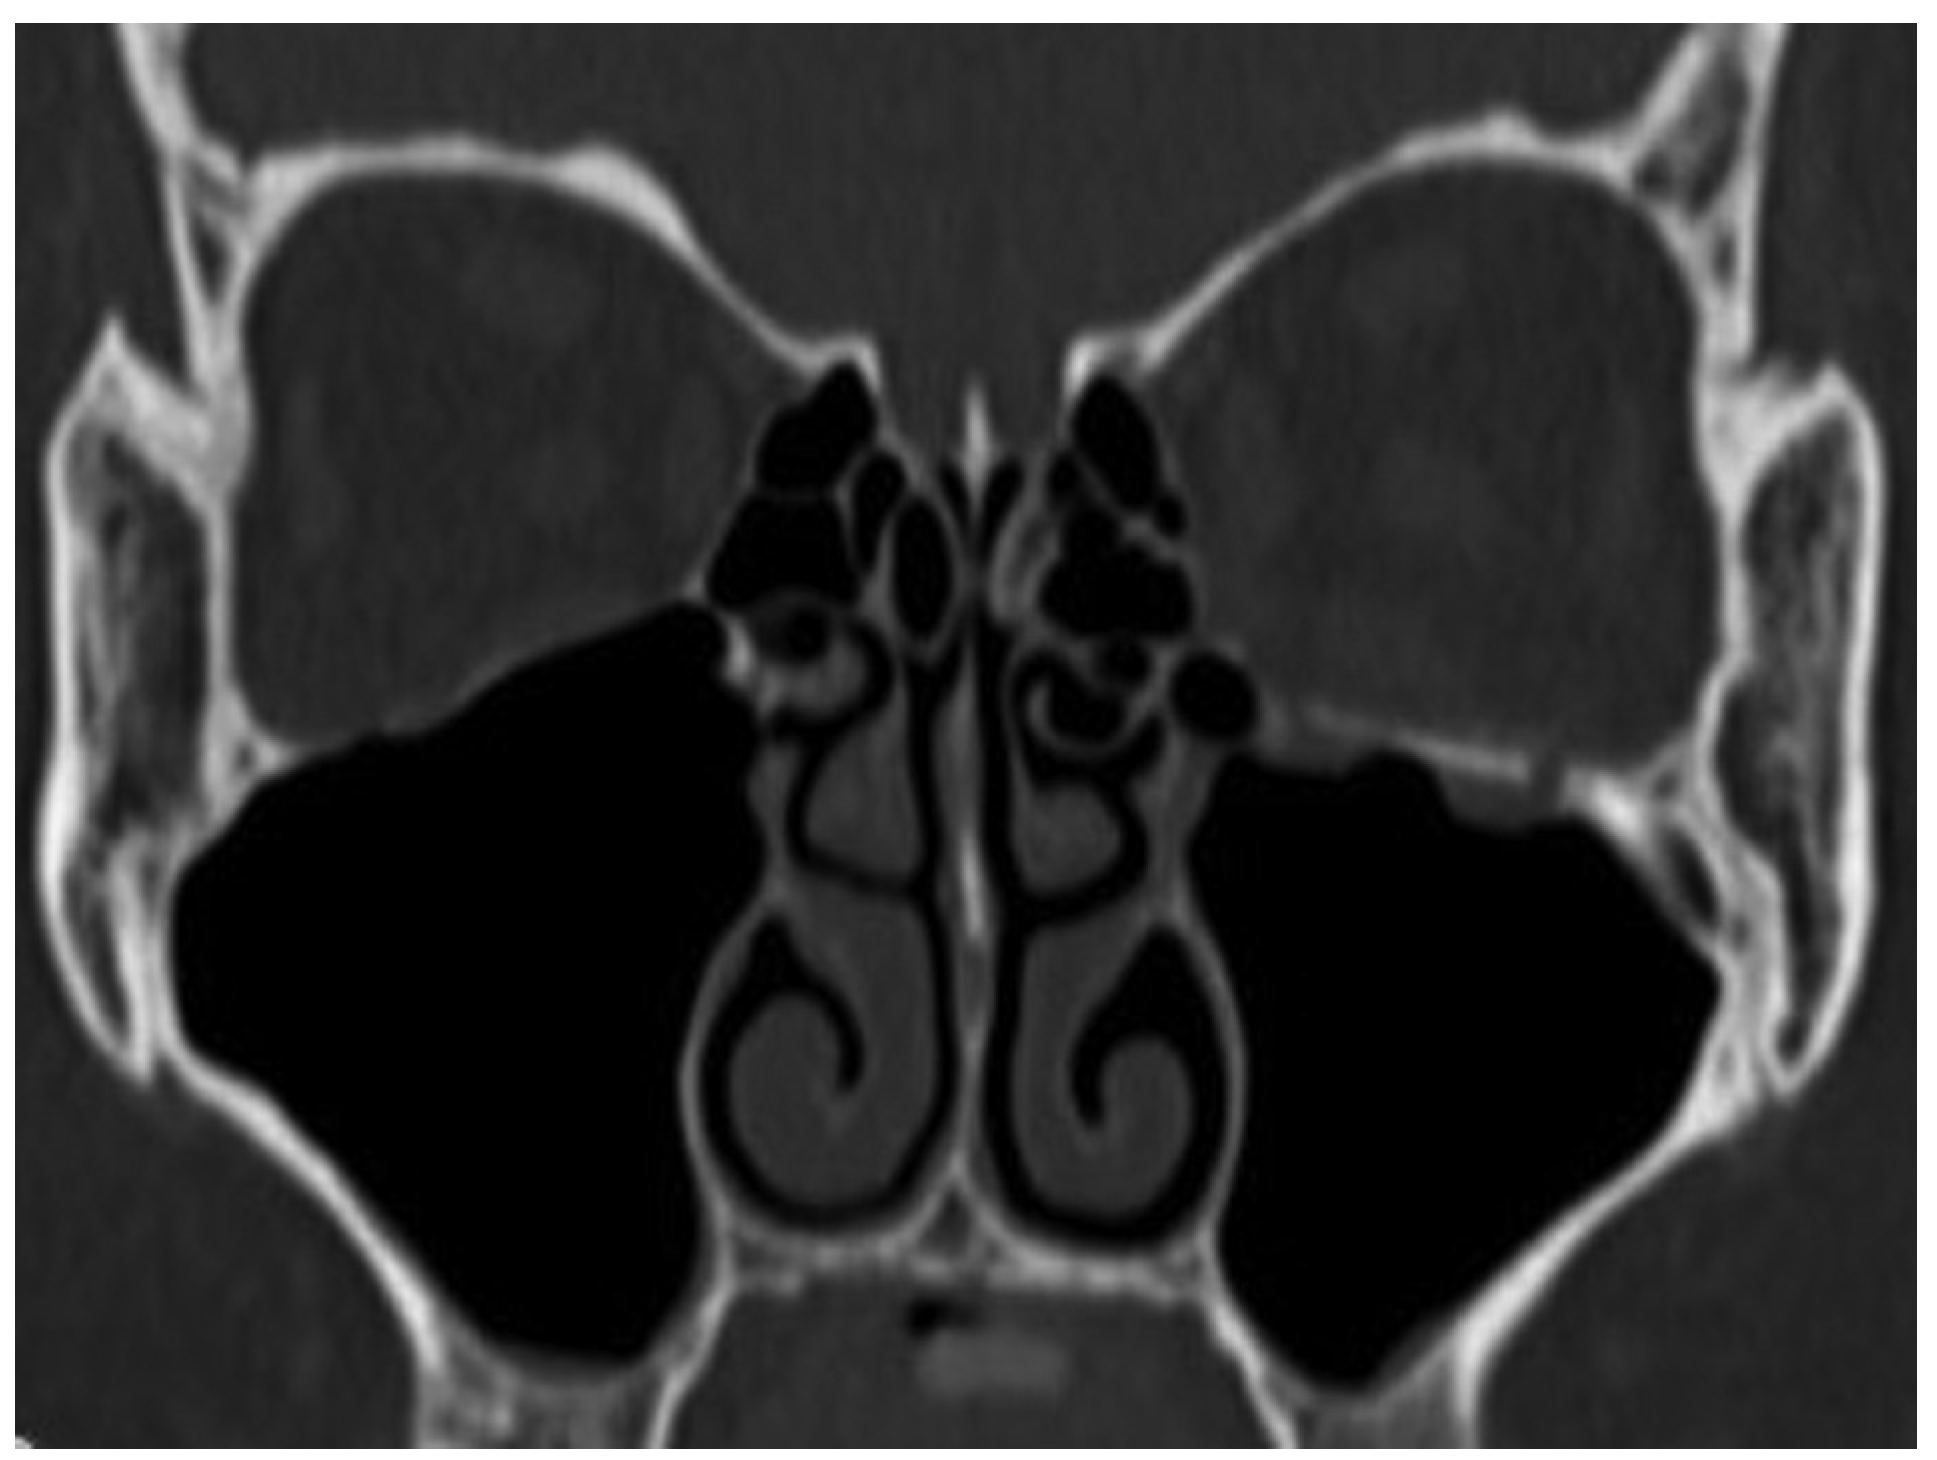

Case 24

A 26-year-old man was found in need of an urgent surgery with missing medial rectus muscle with nausea and vomiting. He sustained facial injuries in a car accident, and presented with diplopia with headache. He was referred to our emergency clinic and was charged to our department for a suspected blowout fracture. CT imaging revealed a fracture of the medial wall of the punched-out type and also the absence of medial rectus muscle on the orbital medial wall (Figure 7). The patient’s left eye movements—medial gaze and lateral gaze—were severely restricted. The diagnosis was a blowout fracture with the punched-out type of the orbital medial wall. Immediate surgery was performed to release the strangulated muscle at 11 hours after injury. His left eye was locked to medial side under general anesthesia (Figure 8).

Figure 7. Axial view of orbit in blowout fracture (entrapment type). Medial rectus muscle locked between fractures and inception of ischemia in rectus muscle.